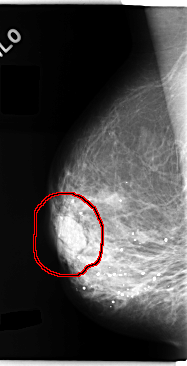

C_0145_1.RIGHT_MLO

FILE: C_0145_1.RIGHT_MLO.OVERLAY

TOTAL_ABNORMALITIES 1

ABNORMALITY 1

LESION_TYPE MASS SHAPE LOBULATED MARGINS CIRCUMSCRIBED

ASSESSMENT 4

SUBTLETY 5

PATHOLOGY BENIGN

TOTAL_OUTLINES 1

BOUNDARY